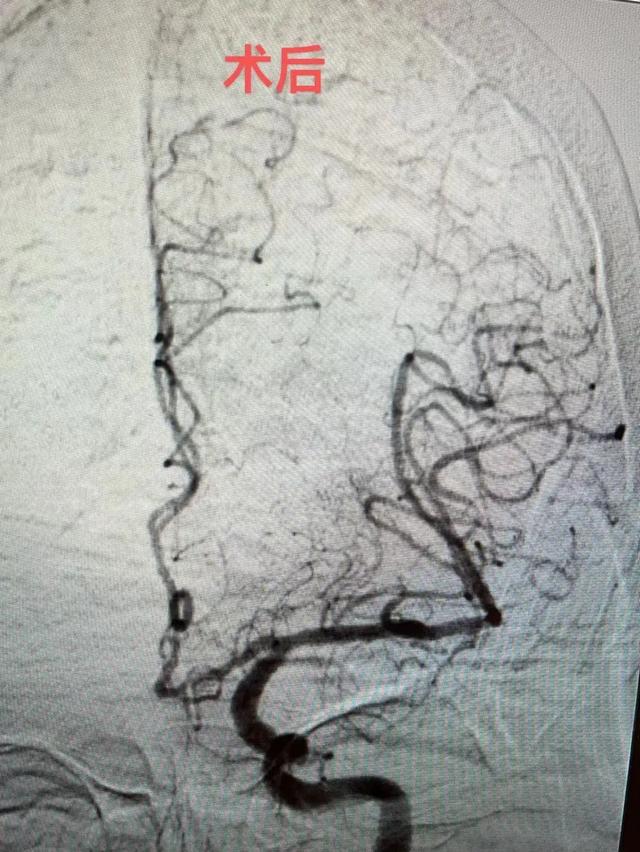

介入导管室一键启动,麻醉科配合采用局麻+药物联合麻醉,缪桂华副主任医师带领团队通过股动脉置管建立手术取栓通道,考虑血栓负荷量大,小心探查,由近及远行ADAPT技术抽吸出血栓主体,颅内残余血栓采用抽吸导管及支架钳夹出来,最终在错综复杂的血管“迷宫”中,找到了一条“生命通道”,手术时间仅用1小时左右,石奶奶被收住入神经内科监护病房继续救治。